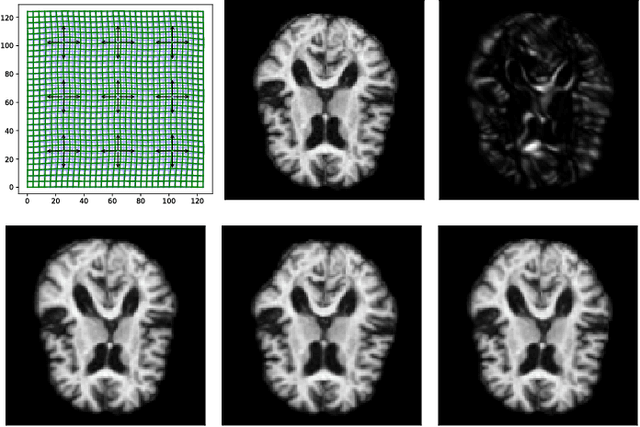

Abstract:Models of stochastic image deformation allow study of time-continuous stochastic effects transforming images by deforming the image domain. Applications include longitudinal medical image analysis with both population trends and random subject specific variation. Focusing on a stochastic extension of the LDDMM models with evolutions governed by a stochastic EPDiff equation, we use moment approximations of the corresponding Ito diffusion to construct estimators for statistical inference in the full stochastic model. We show that this approach, when efficiently implemented with automatic differentiation tools, can successfully estimate parameters encoding the spatial correlation of the noise fields on the image

Abstract:Modelling deformation of anatomical objects observed in medical images can help describe disease progression patterns and variations in anatomy across populations. We apply a stochastic generalisation of the Large Deformation Diffeomorphic Metric Mapping (LDDMM) framework to model differences in the evolution of anatomical objects detected in populations of image data. The computational challenges that are prevalent even in the deterministic LDDMM setting are handled by extending the FLASH LDDMM representation to the stochastic setting keeping a finite discretisation of the infinite dimensional space of image deformations. In this computationally efficient setting, we perform estimation to infer parameters for noise correlations and local variability in datasets of images. Fundamental for the optimisation procedure is using the finite dimensional Fourier representation to derive approximations of the evolution of moments for the stochastic warps. Particularly, the first moment allows us to infer deformation mean trajectories. The second moment encodes variation around the mean, and thus provides information on the noise correlation. We show on simulated datasets of 2D MR brain images that the estimation algorithm can successfully recover parameters of the stochastic model.

Abstract:Matching of images and analysis of shape differences is traditionally pursued by energy minimization of paths of deformations acting to match the shape objects. In the Large Deformation Diffeomorphic Metric Mapping (LDDMM) framework, iterative gradient descents on the matching functional lead to matching algorithms informally known as Beg algorithms. When stochasticity is introduced to model stochastic variability of shapes and to provide more realistic models of observed shape data, the corresponding matching problem can be solved with a stochastic Beg algorithm, similar to the finite temperature string method used in rare event sampling. In this paper, we apply a stochastic model compatible with the geometry of the LDDMM framework to obtain a stochastic model of images and we derive the stochastic version of the Beg algorithm which we compare with the string method and an expectation-maximization optimization of posterior likelihoods. The algorithm and its use for statistical inference is tested on stochastic LDDMM landmarks and images.

Abstract:We introduce a stochastic model of diffeomorphisms, whose action on a variety of data types descends to stochastic evolution of shapes, images and landmarks. The stochasticity is introduced in the vector field which transports the data in the Large Deformation Diffeomorphic Metric Mapping (LDDMM) framework for shape analysis and image registration. The stochasticity thereby models errors or uncertainties of the flow in following the prescribed deformation velocity. The approach is illustrated in the example of finite dimensional landmark manifolds, whose stochastic evolution is studied both via the Fokker-Planck equation and by numerical simulations. We derive two approaches for inferring parameters of the stochastic model from landmark configurations observed at discrete time points. The first of the two approaches matches moments of the Fokker-Planck equation to sample moments of the data, while the second approach employs an Expectation-Maximisation based algorithm using a Monte Carlo bridge sampling scheme to optimise the data likelihood. We derive and numerically test the ability of the two approaches to infer the spatial correlation length of the underlying noise.